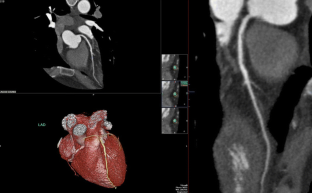

Fig. 1